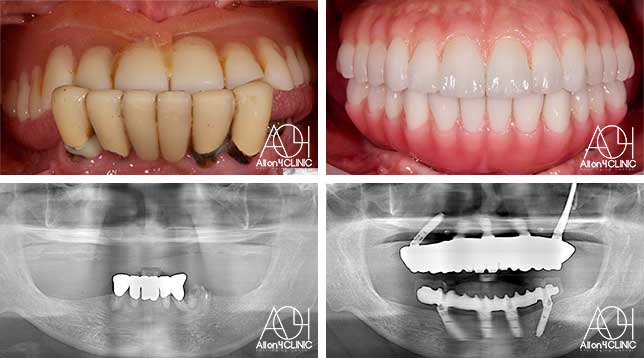

女性 / 62歳

入れ歯が合わなく痛いし、入れ歯を入れている事が嫌になってしまった。

治療詳細: X-guide(エックスガイドナビゲーションシステム)を用いてインプラントを正確に埋入。上下オールオン4。

費用:7,920,000(税込)『モニター割引適用』

リスク:治療後の口腔管理が不適切な場合、埋入したインプラント周囲に感染・炎症を起こし、脱落する可能性がございます。